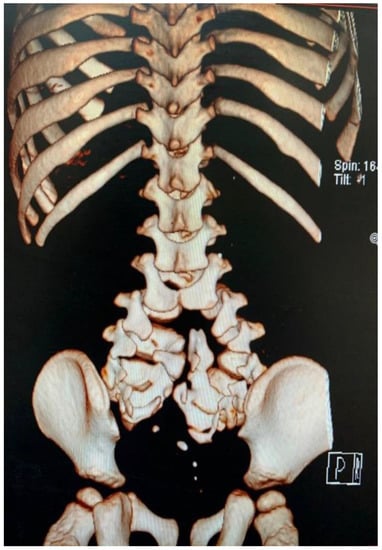

2. Clinical Presentation